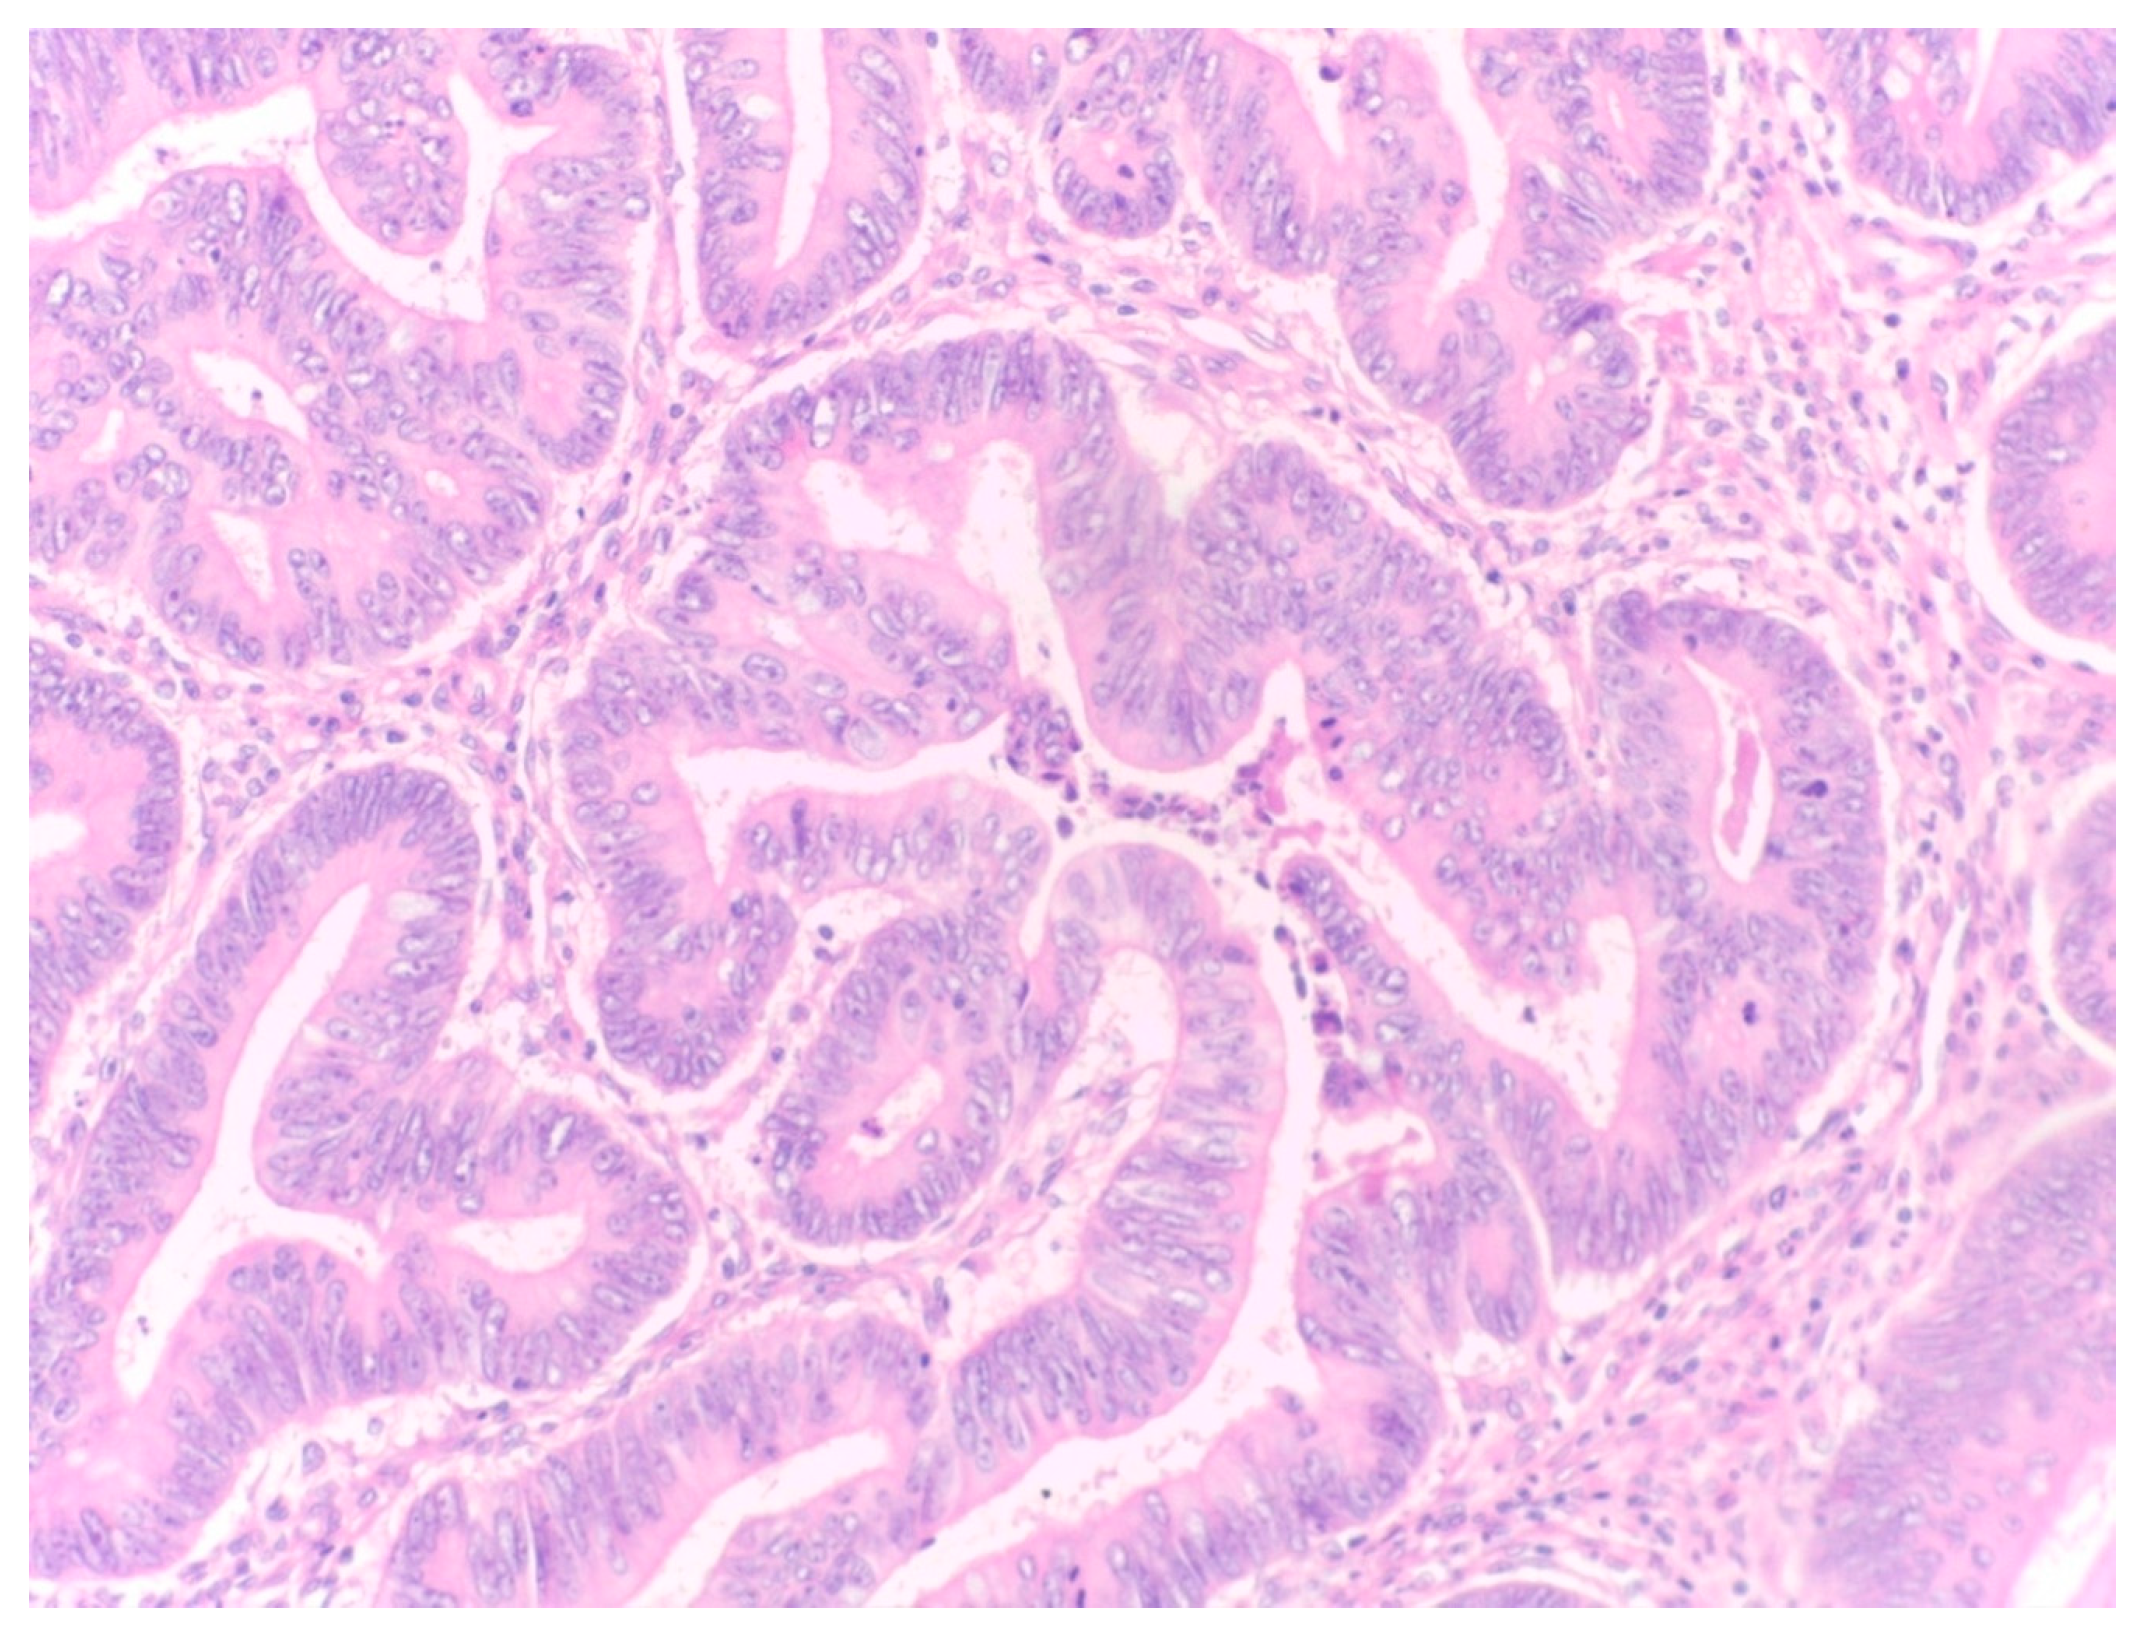

Unselective Measurement of Tumor-to-Stroma Proportion in Colon Cancer at the Invasion Front—An Elusive Prognostic Factor: Original Patient Data and Review of the Literature

2. Materials and Methods